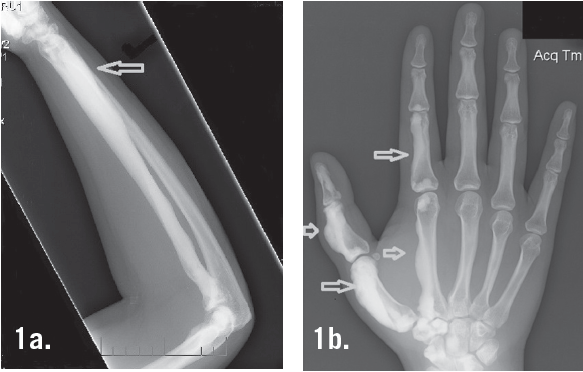

La meloreostosi è una patologia dello sviluppo e una displasia mesenchimale in cui la corticale ossea si allarga e diventa iperdensa in una distribuzione sclerotomica. La condizione inizia durante l'infanzia ed è caratterizzata da un ispessimento delle ossa. Il dolore è un sintomo frequente e spesso l'osso può assumere un aspetto di una cera di candela che gocciola.